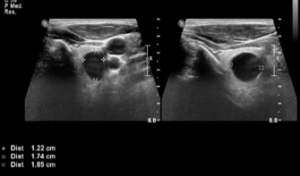

Nodulo tiroideo solido